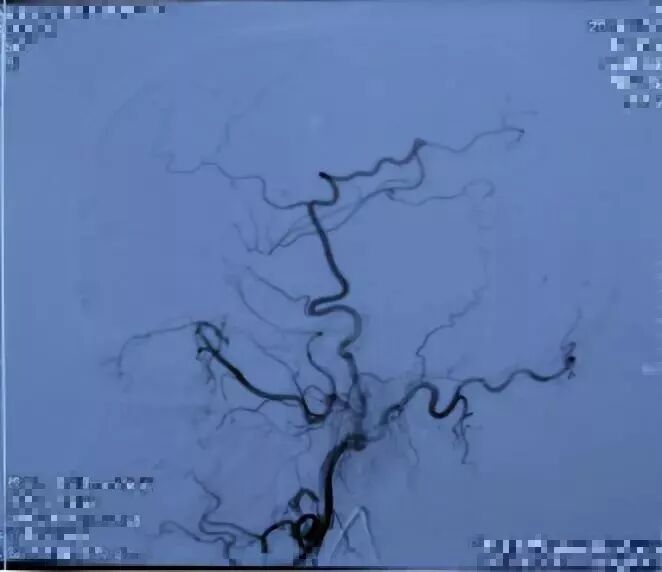

2017.04 DSA R-ICA